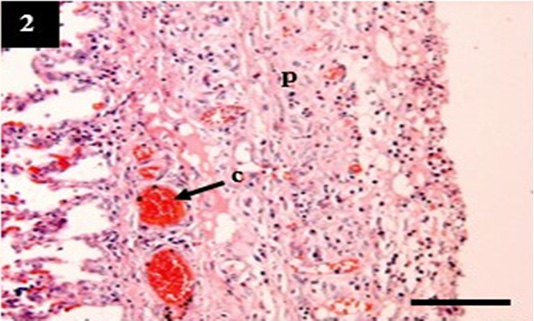

Histopathology of lung from case C4 showed the thickening of the pleural wall (p) and congestion within the venous (c). H&E, 10×.